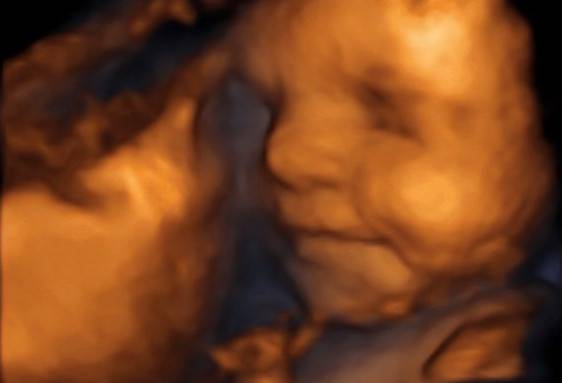

Dr n. Med. Jacek Skórczewski jest specjalistą z zakresu położnictwa i ginekologii. Zajmuje się opieką nad kobietami w ciąży, w tym w ciąży fizjologicznej, jak i powikłanej. W kręgu zainteresowań lekarza leży szczególnie diagnostyka ultrasonograficzna: położnicza i ginekologiczna. Wykonuje również badanie ultrasonograficzne prenatalne pomiędzy 11 a 14 tygodniem ciąży zgodnie z certyfikatem FMF (Fetal Medicine Foundation z siedzibą w Londynie) wraz z komputerową oceną ryzyka indywidualnego.